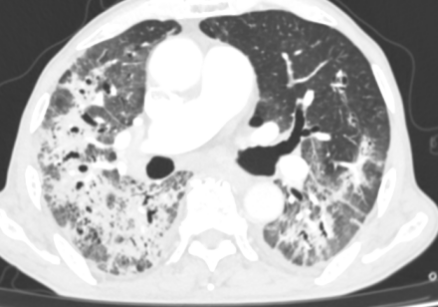

患者王大爷因“咳嗽、胸闷3天,呼吸困难加重5小时”被120紧急送入本部院区就诊。入院时患者高热、呼吸极度困难,肺部听诊可闻广泛Velcro啰音,血气分析提示Ⅰ型呼吸衰竭,胸部CT显示双肺弥漫性结节斑片影。患者有溃疡性结肠炎病史,曾使用激素治疗,初步诊断为重症肺炎。病情危急,医疗团队立即予以高流量氧疗、抗感染及激素治疗,并由贾兆广副主任医师行床旁气管镜检查,送检支气管灌洗液进行tNGS病原学检测。

胸部CT:双肺弥漫结节斑片影